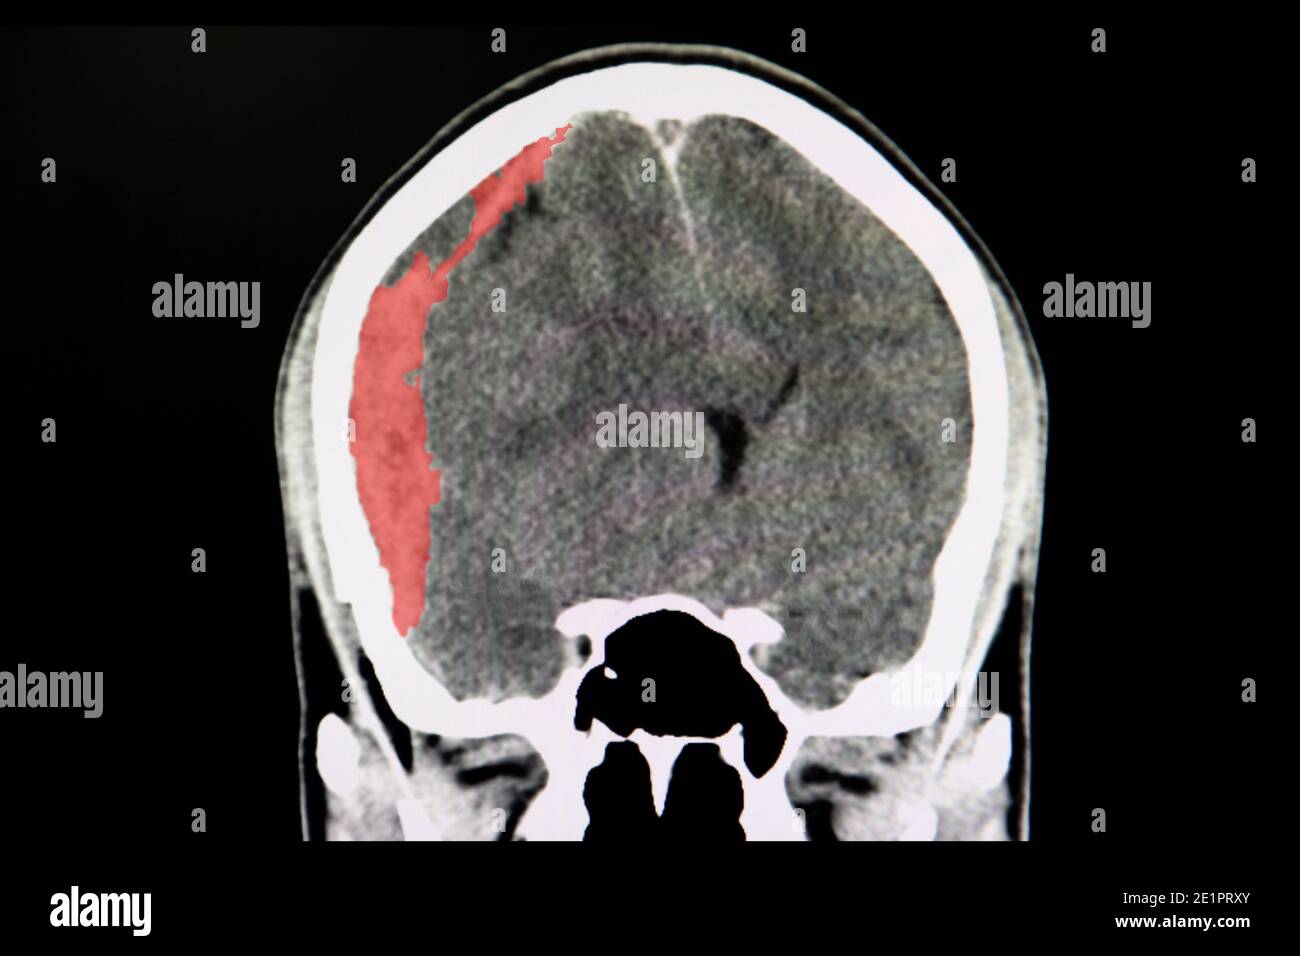

Le recensioni sul reparto di Neurochirurgia ospedaliera dell'Ospedale Civile Maggiore di Verona Borgo Trento, con opinioni e commenti dei pazienti su dottori, medici, infermieri. Ematoma spinale subdurale o epidurale Siringomielia del midollo spinale o del tronco encefalico Paraparesi spastica tropicale/mielopatia a virus linfotropo umano 1 Ulteriori contenuti Metti alla prova la tua conoscenza Altri studi neurologici di diagnostica per immagini. Un ematoma subdurale cronico appare ipodenso rispetto al tessuto cerebrale, mentre un ematoma subdurale subacuto può avere una densità radiologica simile al tessuto cerebrale (isodenso) L'ematoma subdurale isodenso, soprattutto se bilaterale e simmetrico, potrebbe apparire solo leggermente anormale.

Ematoma sugaleale se si forma superficialmente tra la membrana connettiva di rivestimento esterno delle ossa (periostio) e il tessuto fibroso che ricopre invece la parte superiore del cranio (galea);. L'ematoma epidurale è molto simile, ma si verifica quando viene a formarsi un'emorragia fra il cranio e lo strato esterno (dura madre) del tessuto che ricopre il cervello (meningi) In caso di ematoma subdurale o epidurale, è necessario ricorrere immediatamente alle cure del medico. Un ematoma subdurale cronico appare ipodenso rispetto al tessuto cerebrale, mentre un ematoma subdurale subacuto può avere una densità radiologica simile al tessuto cerebrale (isodenso) L'ematoma subdurale isodenso, soprattutto se bilaterale e simmetrico, potrebbe apparire solo leggermente anormale.